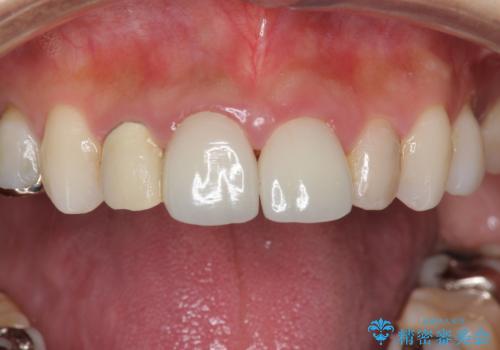

適合が良い被せ物が入りました。

前歯2本同時に行ったため色もピッタリで患者様に満足して頂けました。